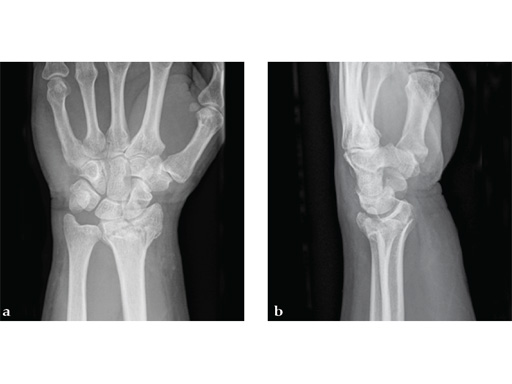

Case 1: A 62-year-old man fell on his outstretched left hand while playing tennis, sustaining an intraarticular fracture of the distal radius, Mller AO Classification 23-C3.2.

Case provided by Renato Fricker, Bruderholz, Switzerland